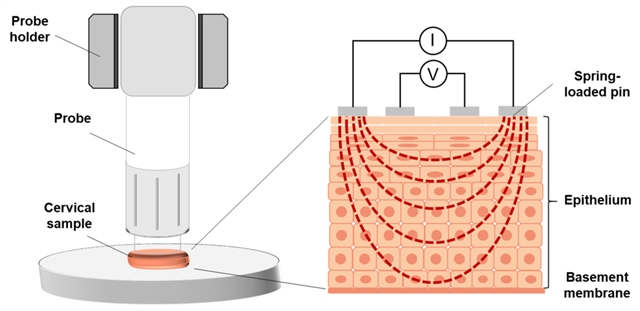

实验装置示意图。

通过适当的筛查和治疗方法成功治疗宫颈上皮内瘤变 (CIN) 可以防止向宫颈癌的发展。作者提出了生物阻抗光谱测量装置和多电极探针作为CIN 的独立筛查工具。为了评估这种筛查方法的性能,作者招募了123名患者,包括69名疑似 CIN 患者和54名无宫颈发育不良的对照患者,他们因良性疾病 (非CIN) 接受了子宫切除术。锥切后,使用基于电生物阻抗光谱的多电极探针表征切除的宫颈组织的电特性。基于电能集中法的灵敏度优化测量方法,通过两个同心阵列电极收集了 28 个多频电压。将CIN组和非CIN组的电特性与病理报告的结果进行比较。随着频率的增加,CIN和非CIN组的重建电阻率趋于降低。从625 Hz 到50 kHz 的重建电阻率在CIN组和非CIN组之间存在显着差异 (p<0.001)。使用100 kHz作为参考,CIN组和非CIN组之间的差异是显着的。基于100 kHz与其他频率重建电阻率的差异,该方法在CIN筛查中的灵敏度为94.3%,特异性为84%,准确率为90%。通过使用基于电生物阻抗谱的多电极筛查探针在切除组织中评估的频谱差异,证实了无创CIN筛查的可行性。